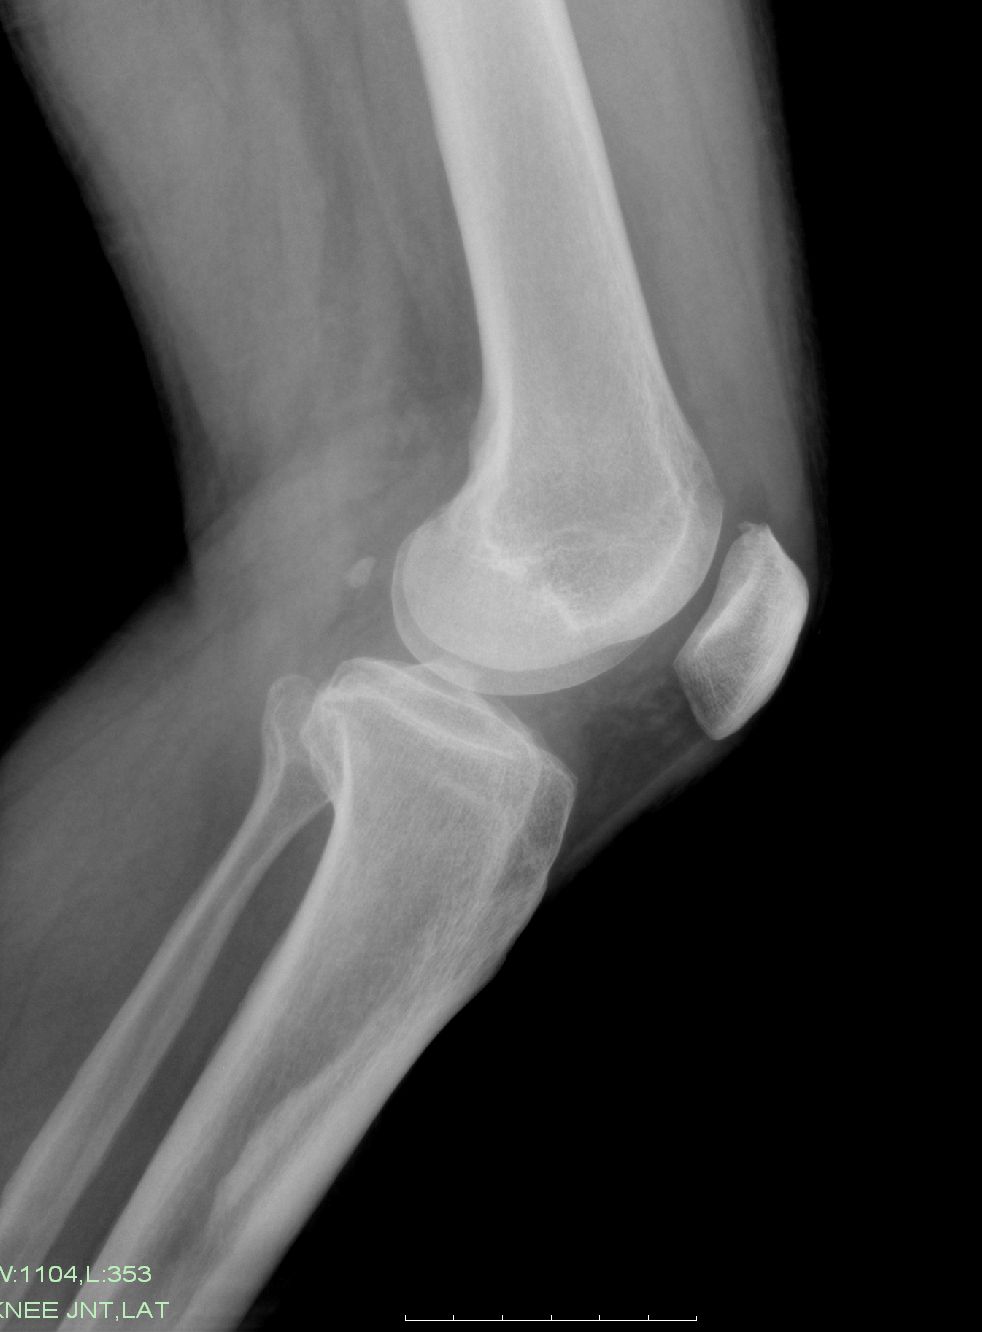

以下是引用zxl51642在2009-9-4 10:43:00的发言:[br]1、关节退变,2、局限性骨皮质增厚,无意义,长期观察,必要时mri。

以下是引用zjzjr在2009-9-4 16:06:00的发言:[br]局限性骨皮质增厚,轻度退行性变

以下是引用黑白光影在2009-9-4 14:38:00的发言:[br]膝关节构成骨有轻度退行性改变,胫骨上段前内侧局限性骨皮质增厚,正如6楼所说。